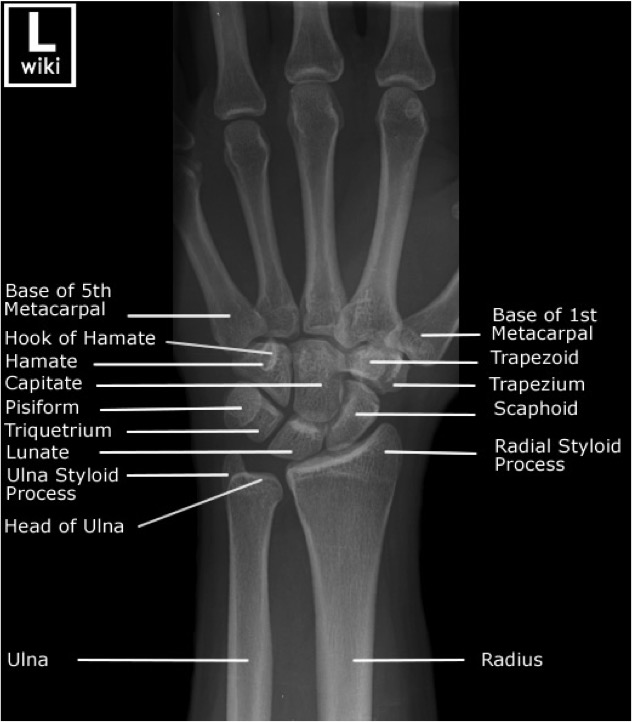

Wrist and Hand1 Radiology Key Radius Radiology Use the many eponyms with caution. Fractures of the distal radius are common and result from both high and low energy trauma. Typical fracture patterns arise in the. Forearm fractures are characteristic depending on patient age. Gp referrals, nhs patients and private patients can benefit from advanced imaging services, including angiography, fluoroscopy, computerised tomography (ct), magnetic. Learn about the epidemiology,. Radius Radiology.